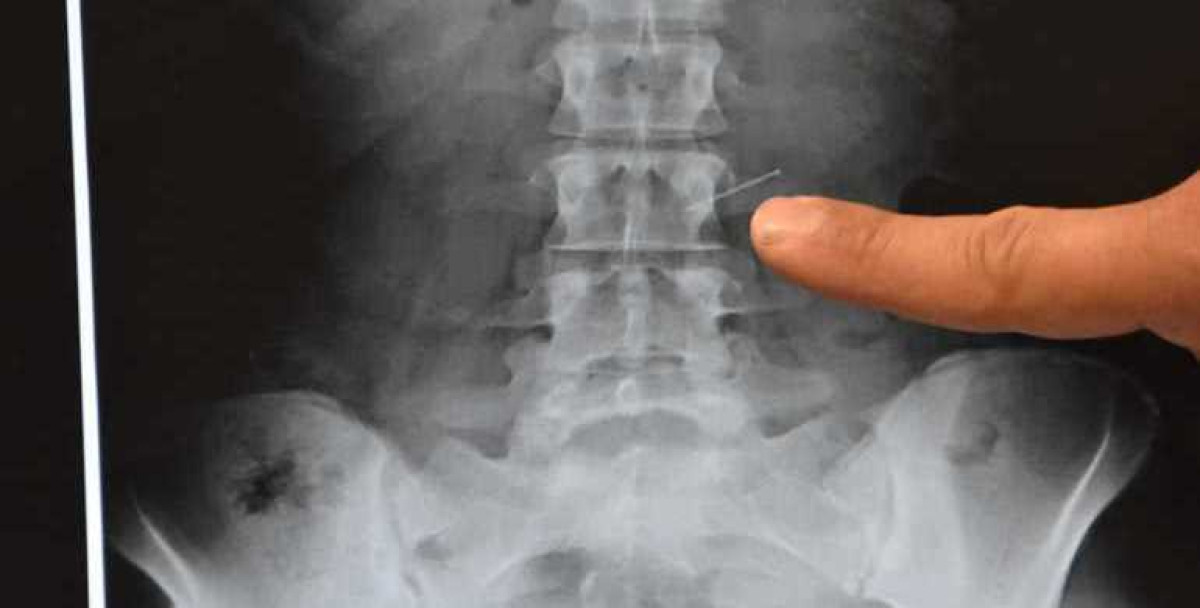

Осужденный за кражу житель Балхаша Азамат Адеубеков проглотил пять гвоздей и пять иголок. Сделал он это в знак протеста действиям суда, который дал ему всего пять дней для ознакомления с уголовным делом, тогда как он просит предоставить значительно больше времени, передает BaigeNews.kz со ссылкой на nv.kz.

В департаменте уголовно-исполнительной системы Карагандинской области подтвердили, что осужденный проглотил острые предметы.

"Азамат Адеубеков, осужденный по статье 188 Уголовного кодекса (Кража), объявил о том, что проглотил инородные предметы, поскольку не согласен был с вынесенным в отношении него приговором суда. Незамедлительно осмотрен хирургом, проведены рентген-обследования. На момент осмотра острая патология не выявлена. Находится под наблюдением медицинских сотрудников учреждения", − сообщил руководитель пресс-службы департамента УИС Карагандинской области Рустам Каюпов.